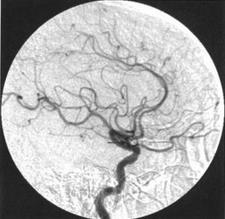

自发性蛛网膜下腔出血; 是一种常见的出血性脑血管病 ,预后差。美国心脏病学会近来的报告显示,SAH 总死亡率约为25 % ,存活者中 50%有明显的并发症 ,且这些并发症多与SAH 后继发的脑血管痉挛; 有关。CVS 发生率由于缺乏恒定、可靠的诊断标准而差异很大 ,约一半病例 CVS 表现为延迟性的脑缺血障碍 ,严重时发展成为脑梗塞。虽经最大努力治疗 ,仍有一部分病人由于CVS 而发生脑卒中或死亡。动态CT脑灌注成像是研究蛛网膜下腔出血后脑血管痉挛的重要手段之一。2015年2月,在发表《Arq Neuropsiquiatr.》的一篇文章中,研究人员建立了一个适用于研究脑血管的自身调节的蛛网膜下腔出血后脑血管痉挛的体外模型。研究人员进一步调查了含碘对比剂碘克沙醇对痉挛性脑血管的血管张力和肌原性反应的影响。

动态CT脑灌注成像是研究蛛网膜下腔出血后脑血管痉挛的重要手段之一,但对比剂的使用可能会影响脑血流的微循环,进而影响疾病的预后。但该项研究显示,等渗对比剂碘克沙醇对SAH后血管张力或肌原性反应无不良影响,安全性良好。 (环球医学资讯供稿 责任编辑 :Ada) 参考资料:http://www.ncbi.nlm.nih.gov/pubmed/25742582